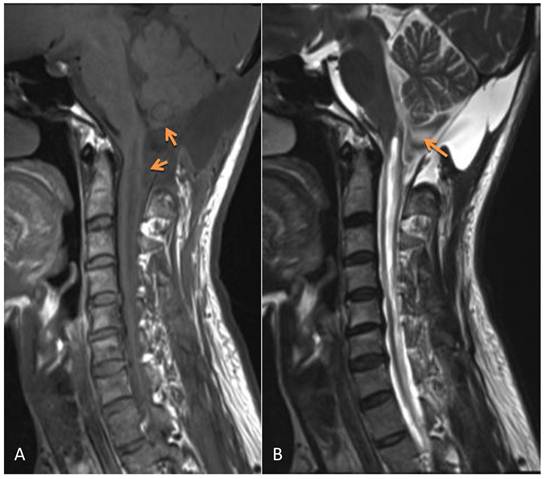

The postoperative symptoms were slightly improved compared to pre-surgery. The results of pathological examination showed that the wall of the cyst was composed of fibrous tissue but without epithelial cells; the diagnosis of arachnoid cyst was made (Figure 2). During three months of follow-up, the condition of this patient continued to improve with normal urination and bowel function and good daily self-management. Physical examinations showed that superficial sensation was gradually diminished and muscle power of upper and lower limbs increased to grade V. Tendon reflex was normal, however, there was no improvement in muscle wasting. MRI re-examination showed that the arachnoid cyst still remained, however, its size appeared slightly smaller than that before surgery. Although the compression on the cerebellar tonsil, pons and cervical spinal cord was reduced, the size of the syrinx was still the same as before surgery (Figure 3).

Figure 3

MRI 3 months after surgery shows the remaining arachnoid cyst (which was slightly smaller than before surgery), the compression on the cerebellar tonsil, the reduced pons and cervical spinal cord. However, the syrinx was the same as presurgery. A: T1WI; B: T2WI.